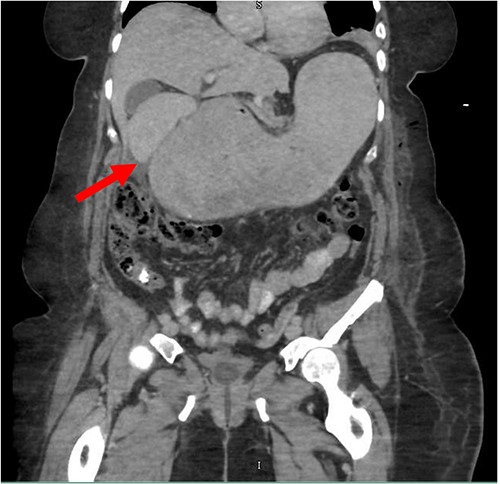

Despite the insertion of the NGT yielding 1500 cc output in 24 hours, the patient continued to experience severe abdominal pain. Urgent abdominal and pelvic computed tomography (CT) scans were taken, as seen in Figs 2–4. The CT scans showed gastric distension and the spleen positioned anteriorly in the right upper quadrant. Consequently, the decision was made to promptly bring the patient to the operating room for a diagnostic laparoscopy with plan to detorse the spleen.

CT of the abdomen and pelvis (coronal slice) showing gastric distention and the spleen positioned in the right upper quadrant.